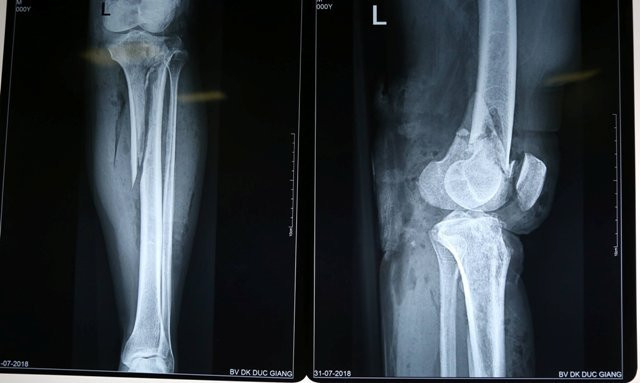

Bệnh nhân L.T.P được phẫu thuật thành công sau tai nạn. (Ảnh: BVCC)

Kết quả chẩn đoán cho thấy, bệnh nhân P bị gãy hở lồi cầu đùi và xương chày trái cùng tổn thương động mạch khoeo cần phải phẫu thuật. Sau hơn 1h, ca phẫu thuật cho bệnh nhân kết thúc. Hiện tại, anh P tỉnh táo nhưng bị mất máu nhiều.

Bác sĩ Phan Văn Thành, bác sĩ điều trị cho anh P. thông tin, trong trường hợp của bệnh nhân này việc đầu tiên cần phải làm là cố định xương sau đó mới tiến hành cứu mạch máu. Chân bệnh nhân sẽ được bó bột giúp lành xương, khi ổn định bệnh nhân sẽ tập vận động chân dần cho quen cảm giác.